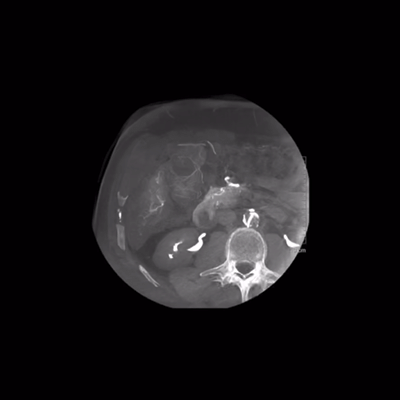

精確的3D成像

簡(jiǎn)單而精確的3D成像,在其臨床中任何病例都可以應(yīng)用,可生成具有空間和軟組織分辨率的3D采集。

圖片來源于:西門子官網(wǎng)

其憑借95°s的旋轉(zhuǎn)速度,ARTIS icono ceiling 系統(tǒng)只需2.5秒即可獲取syngo DynaCT圖像,這意味著更少的運(yùn)動(dòng)偽影。